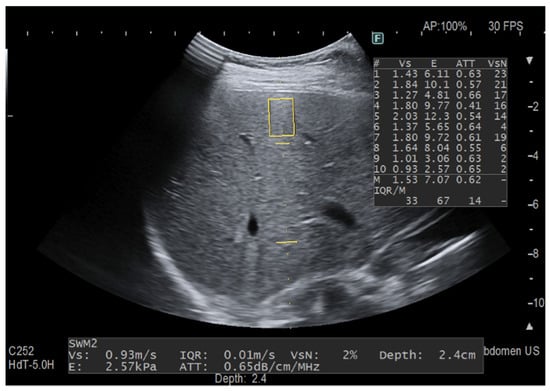

Figure 3.

The measurement was taken focusing on the best image for iATT without following the protocol for stiffness assessment. The two horizontal yellow lines graphically show the width (length of each line) and the length (distance between the two lines) of the iATT measurement area, which has a fixed size (length of 4 cm, from 35 to 75 mm from the skin). The yellow rectangle is the region of interest (ROI) for stiffness measurement. Because it is not possible to exclude the stiffness measurement, the stiffness ROI was intentionally positioned close to the liver capsule. This explains the huge variability between consecutive stiffness measurements with an IQR/M = 67% and a VsN always <50%.